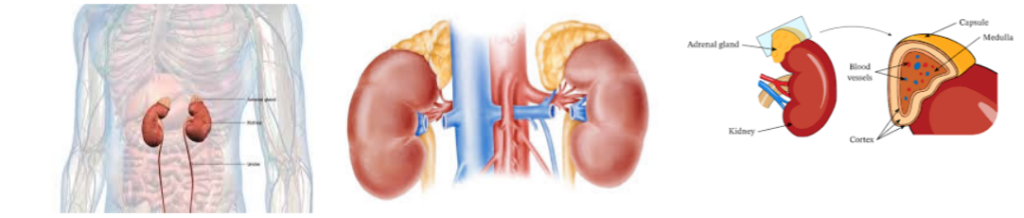

L’importance de la santé des glandes surrénales

Les glandes surrénales sont essentielles à la gestion du stress, à la régulation de l’énergie et au maintien du métabolisme et du système immunitaire. Cependant, des facteurs comme le stress chronique, une mauvaise alimentation, les médicaments et le vieillissement peuvent perturber leur fonctionnement et entraîner des déséquilibres hormonaux.

Les affections courantes causées par un déséquilibre surrénalien comprennent :

- Maladie d’Addison : Production insuffisante de cortisol et d’aldostérone, entraînant fatigue, perte de poids et hypotension artérielle.

- Syndrome de Cushing : Production excessive de cortisol, souvent due à la prise de stéroïdes, entraînant hypertension artérielle, prise de poids et sautes d’humeur.

- Fatigue surrénalienne : Un stress prolongé épuise la fonction surrénalienne, entraînant fatigue chronique, troubles du sommeil et affaiblissement du système immunitaire.